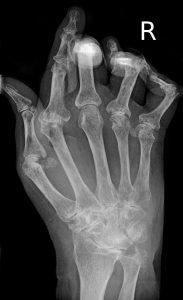

Больных ревматоидным артритом можно выделить даже среди многочисленной толпы людей.

Болезнь поражает не только суставы, снижая их функциональные возможности, но и поражает внутренние органы, в том числе увеличивает риск сердечно-сосудистых заболеваний. Общепризнано, что боль, ухудшение функций суставов, снижение материального состояния влияет и на психоэмоциональный статус: